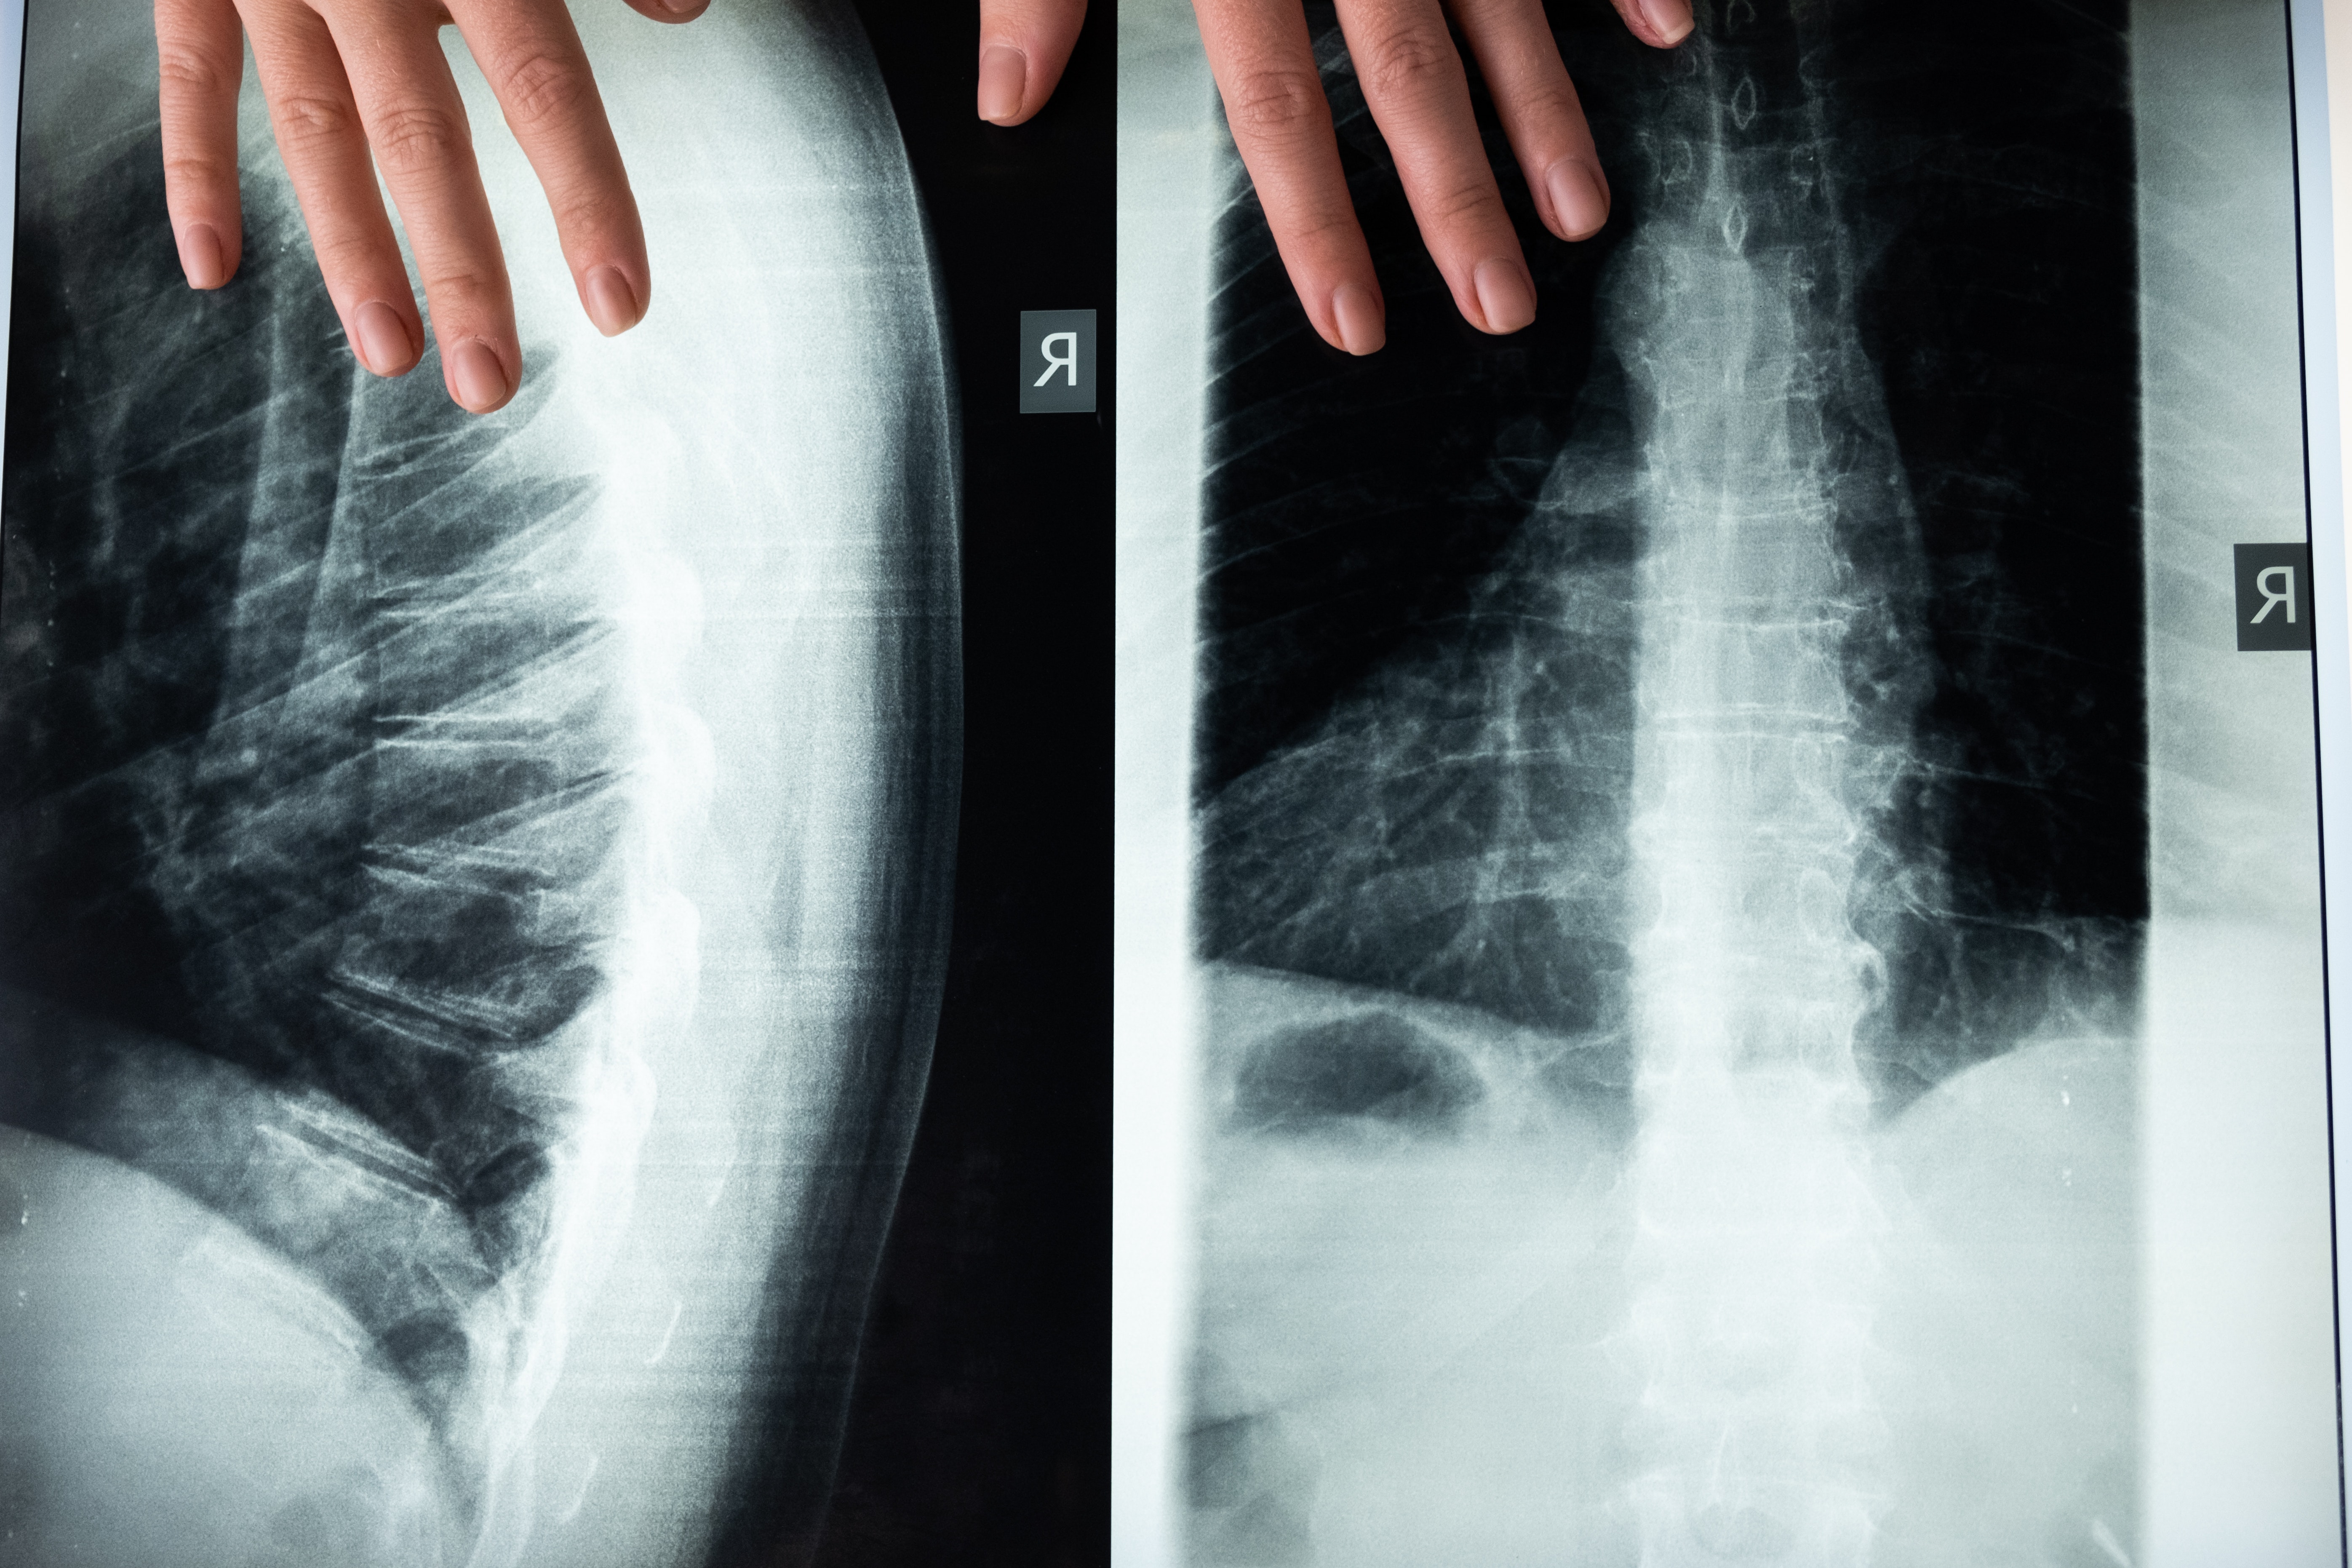

허리디스크(척추 간판 탈출증)는 척추의 간판이 약해져서 주변의 신경을 누르게 되어 발생하는 질환입니다. 이로 인해서 통증이나 신경에 증상이 발생할 수가 있습니다 허리디스크 환자에게는 무리하지 않는 운동이 중요합니다. 그렇지 않으면 상황이 악화될 수가 있습니다.